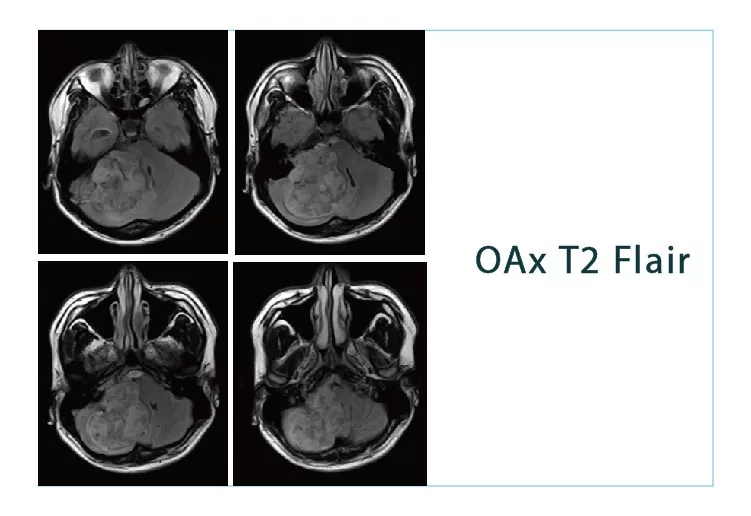

【朗润影像档案】磁共振影像病例分享(编号20180831)